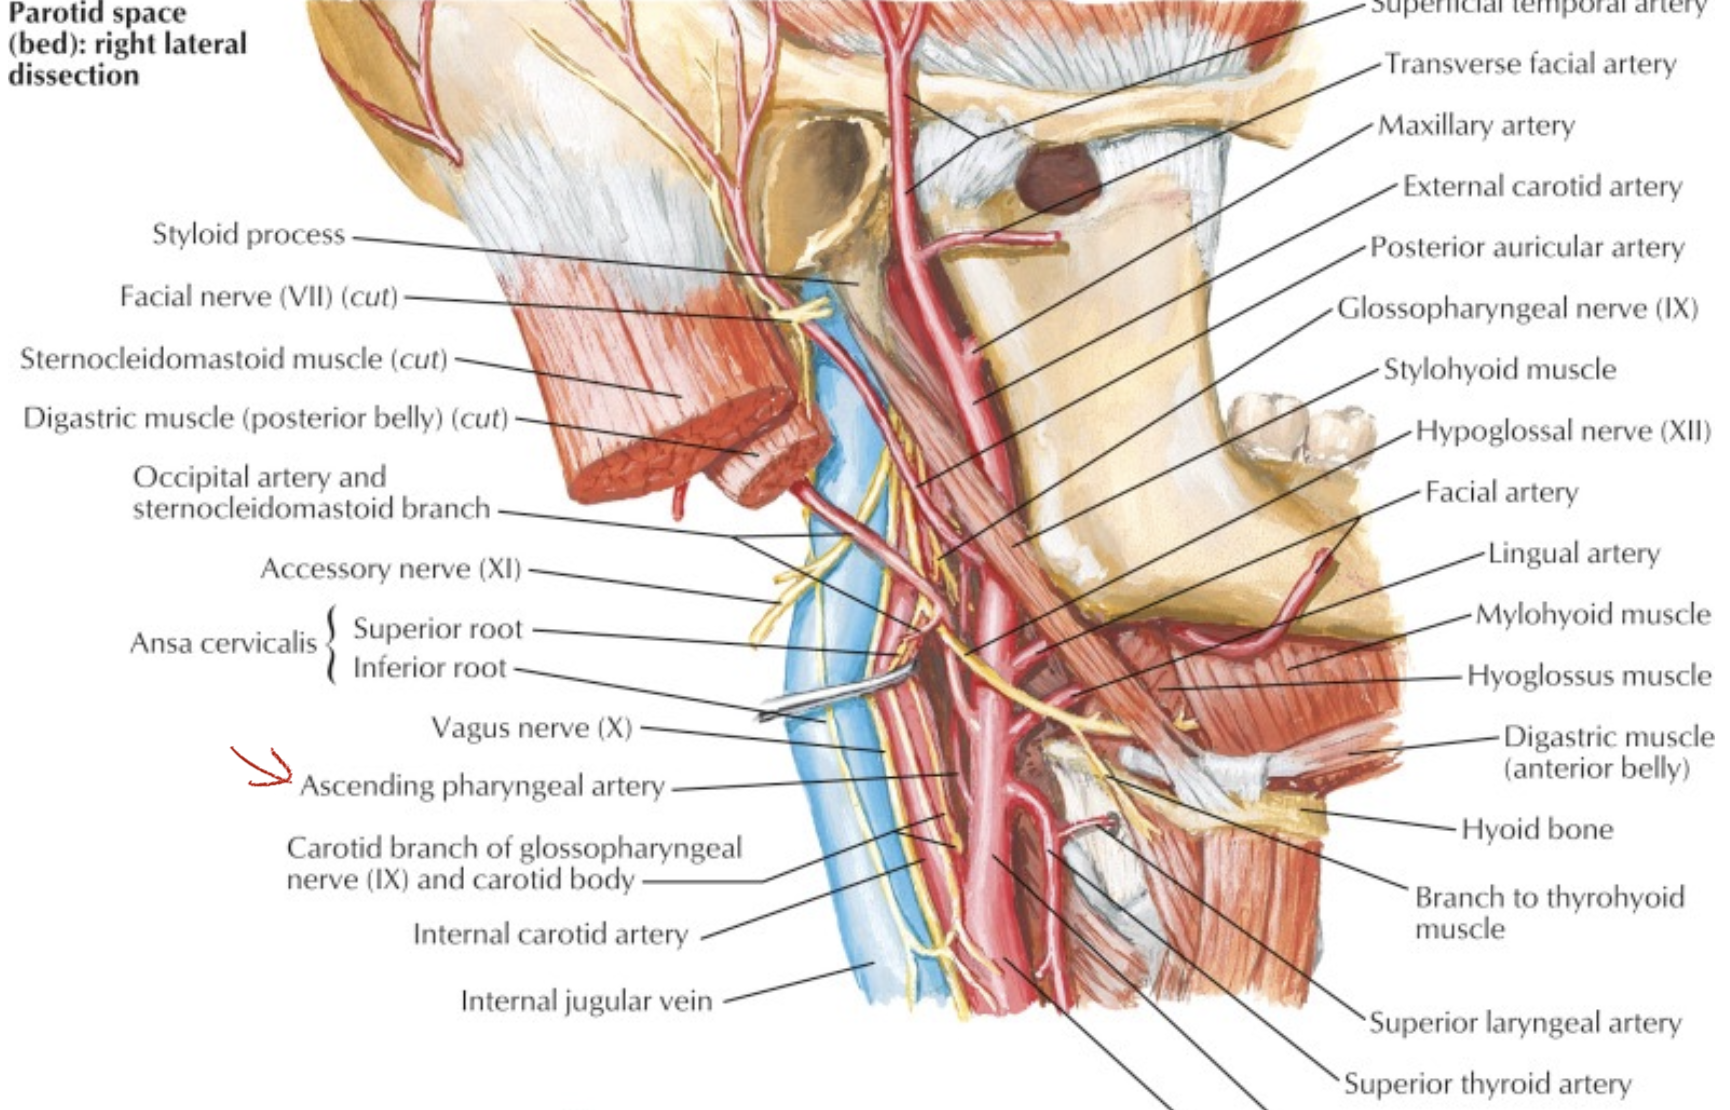

External carotid

- lingual a.

- hyoglossus m. 深層,digastric下

- Superficial temporal a.

- 從耳前上穿出

Facial a.

digastric上

Ascending palatine a.

- Styloglossus, Stylopharyngeus m. 之間,levator veli palatini m.附近分兩支:

- 支配軟顎

- 支配palatine tonsil, auditory tube

Maxillary a.

Superior thyroid artery

- Infrahyoid br.

- Sup. laryngeal a.

- SCM br.

- Cricothryoid br.

Internal carotid a.

- 進入carotid canal 前無分支

- CN X 伴行

CN X

Structure

- common carotid a. 外側,蓋在 thyrocervical trunk 上

- 跨過ECA所有分支,除了Occipital a.